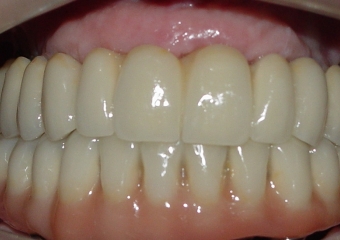

Imagem Próteses Fixas Definitivas Superior e Inferior, em 2013 - Clínica Cliniface

Imagem Próteses Fixas Definitivas Superior e Inferior, em 2013